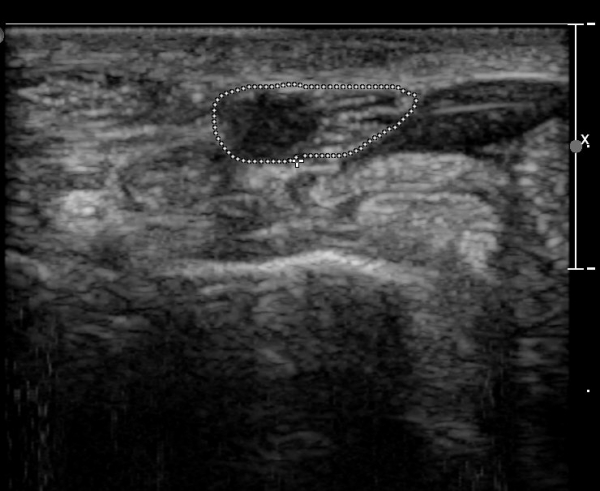

ÃÊÀ½ÆÄ ¼Ò°ß :  ¼Õ¸ñ±ÙÀ§ºÎ Ⱦ´Ü¸é°Ë»ç¿¡¼­ ¼Õ¸ñ±¼±Ù°Ç(FCR)°ú Ç¥Ãþ ¼Õ°¡¶ô ±ÁÈû±Ù(FDS) »çÀÌ¿¡

Á¤Á߽ŰæÀÌ Á¤»óÀûÀÎ ¾ç»óÀ¸·Î º¸ÀÓ(»çÁø 1).

Å½ÃËÀÚ¸¦ ¸»´ÜÀ¸·Î À̵¿ÇÏÀÚ  Á¤Áß½Å굥 ¿äÃø ÀϺΰ¡ Àú¿¡ÄÚ Á¾±«·Î °üÂûµÊ(»çÁø 2).

ÀÌ·± ¸ð½ÀÀº ¼Õ¸ñÀÇ ¿ù»ó°ñ ºÎÀ§(»çÁø 3, 4)¸¦ Áö³ª ¼ö±Ù°ü ±ÙÀ§ºÎ ±îÁö À̾îÁü(»çÁø 5).

ÇÏŰ½ºÆ½(°íÁÖÆÄ) ŽÃËÀÚ¸¦·Î °üÂûµÈ ¸ð½À¿¡¼­ Á¤Áß½Å°æ ºÎºÐ ½Å°æ´Ù¹ßÀÇ Àú¿¡ÄÚ

º¯È­°¡ ¶Ñ·ÈÇÔ(»çÁø 6, 7).

Á¤Á߽Űæ Á¾´Ü¸é°Ë»ç¿¡¼­µµ ¼Õ¸ñ ¸»´ÜºÎ¿¡¼­ ¼ö±Ù°ü ±ÙÀ§ºÎ±îÁö À̾îÁø Àú¿¡ÄÚ

Á¾¾çÀÌ °üÂûµÊ(»çÁø 8, 9, 10, 11).